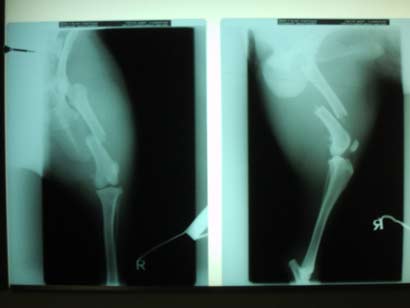

Da Asco sich immer mehr daran gewöhnte auf 3 Beinen zu laufen, hatten wir schon das Schlimmste erwartet und wurden durch ein Röntgenbild leider bestättigt.

Der gebrochene Knochen wuchs einfach nicht zusammen. Es war zu keiner Heilung im Frakturbereich gekommen. Die Frakturenden hatten sich abgedeckelt und waren vollständig instabil. Es war klar, dass Jack mit diesem Bein nie würde laufen können!

Die bittere Diagnose war also eine neuerliche OP, die über eine stärkere Platte, einen stützenden Nagel und zusätzliches, knochenbildendes Gewebe die ersehnte Heilung bringen sollte! Es tut uns in der Seele weh, diesem hochintelligenten und lebensfrohen Hund dies ein weiteres Mal antun zu müssen, aber es half nichts.